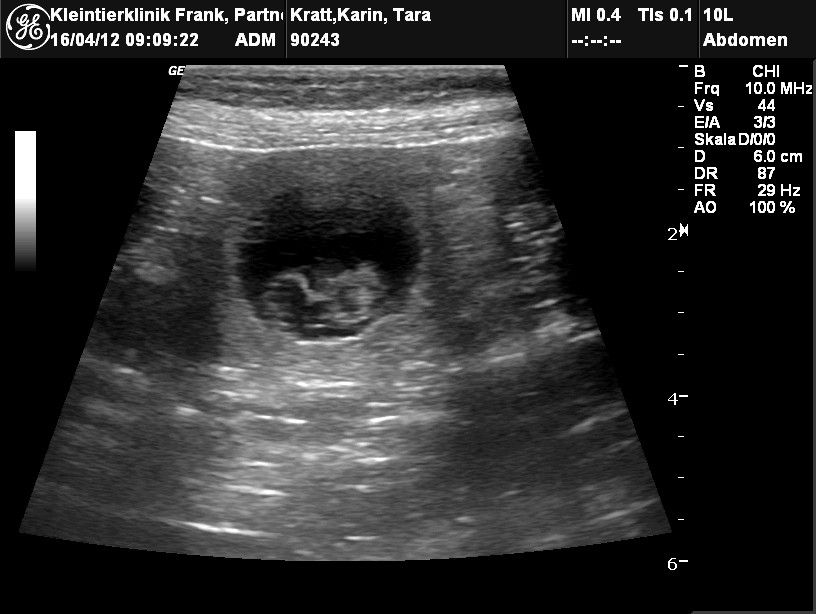

Jetzt ist es amtlich: Tara hat aufgenommen und erwartet Mitte Mai ihre Welpen

Anton “the shooter“ war wieder erfolgreich. Nach seinem letzten Deckakt mit Tara erhielten wir heute das Ultraschallergebnis: WIR SIND SCHWANGER! Also in Fachkreisen heißt das dann: Tara ist „trächtig“!! Da wir aber so menschlich mitfiebern, schreiben wir auch unseren ersten Gedanken hier auf – und somit sind wir schlicht und ergreifend auch schwanger!! :-)